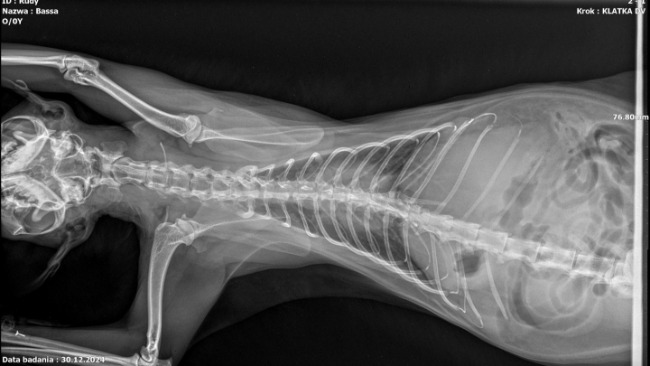

Zaczęło się od Rudego - nasz 6 letni kociak zaczął chorować w listopadzie 2024. Najpierw pojawił się u niego dziwny odruch, jakby wymiotny - diagnoza zakłaczenie, jednak pojawiła się gorączka, zachrypł, był widocznie osłabiony. Antybiotyk oraz kroplówki wniosły chwilową poprawę, wyniki badań były dobre, jednak w Wigilię Bożego Narodzenia Rudzik przestał jeść, zaczął chować się, był bardzo osłabiony, tylko spał. Badania krwi oraz USG nie wykazały nic niepokojącego jednak dalej odmawiał jedzenia i picia - wszystko podawałyśmy mu z mamą za pomocą strzykawki. Diagnoza - stan zapalny dziąseł. Ze względu na okres świąteczny podajemy leki mające na celu zwalczenie stanu zapalnego, stan Rudego się nie poprawia, czekamy na zabieg usuwania kamienia lub ekstrakcji zębów ale w dniu zabiegu stan Rudzika znacznie się zmienił - 30.12.204 zaczęła się żółtaczka, na USG pojawiły się zmiany i powiększenie wątroby, w wynikach bio chemii ostry stan zapalny wątroby, pojawiła się niewielka ilość płynu w jamie brzusznej, RTG wykazało cień w przełyku który chcielibyśmy dalej diagnozować. Rudzik całkiem opadł z sił, zaczął się przewracać i tracić równowagę. 31.12.2024 po podaniu nowych leków zaczął wreszcie sam jeść i pić, wdrożyliśmy karmienie karmami Hepatic by wspomóc jego wątrobę w regeneracji, codziennie wykonywane USG potwierdzało, że płyn w brzuszku przestał się zbierać oraz nie pojawiał się on w płucach. Rudzik do 05.01.2025 codziennie przyjmował antybiotyk, lek na wątrobę, kroplówkę oraz steryd. Wykluczyliśmy takie choroby jak Fiv/Felv oraz toxoplazmozę, wynik na Fip na razie nie był jednoznaczny - stosunek albumin do globulin w dolnej granicy normy.

07.01.2025 Rudasek miał wykonane powtórne badania - morfologia, biochemia, USG oraz RTG

Powtórnie wykonane badanie RTG nie wykazało cienia w przełyku, który był widoczny podczas pierwszego badania.